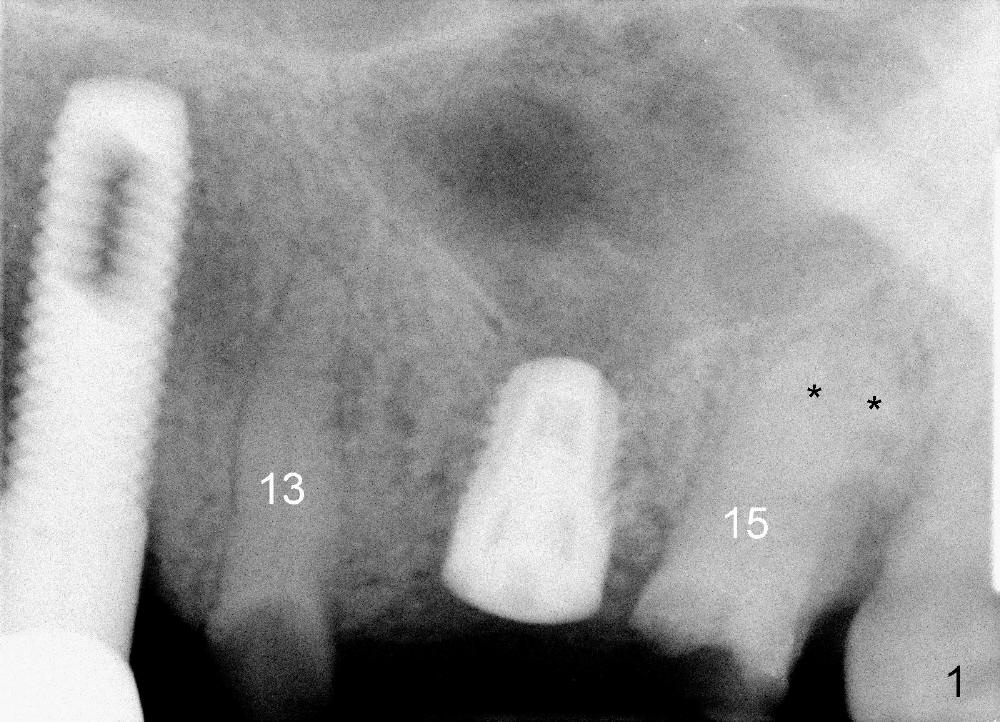

A 84-year-old man has a failing bridge.  A short implant was placed at the pontic site 5 months ago (Fig.1, taken 2 months postop).  The bridge was temporarily recemented.  It is planned at next appointment to extract #13, uncover the implant at pontic and save #15 if possible.  When the bridge is removed, the tooth #15 is also found non salvageable (Fig.2). The root stump of #15 is oval, 5x10 mm.  Preop PA shows that the 2nd molar has two roots (Fig.1: *).  When the tooth is extracted, the septum is found wide buccolingually (Fig.3: S, between the buccal (B) and palatal (P) sockets).  Osteotomy is formed in the septum with combination of drills and osteotomes, followed by insertion of taps (Fig.4).  Finally the osteotomy (Fig.5 O) in the septum (S) of #15 deviates into the buccal (B) socket.  When the implant is placed (Fig.6), it deviates buccally slightly (Fig.7).  The remaining sockets are filled by bone graft (Fig.7 G).  Immediate provisional bridge is fabricated after placement of abutments (A).  The main purpose of the provisional at early stage is to hold bone graft in place.  There is no occlusal contact with the opposing dentition,  Due to time constraint, the uncovering of #14 is postponed.  The provisional dislodges 2-3 days postop.  The patient returns for recementation 5 days postop; the sockets have initially healed (Fig.8,9, as compared to Fig.7).